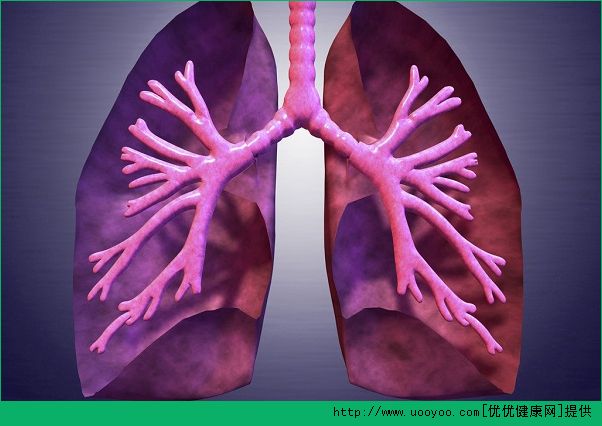

肺炎的發(fā)病率非常高

、免疫減弱由于突然受涼、饑餓

、疲勞2

例如免疫缺陷

病毒可愛(ài)染會(huì)破壞支氣管的粘膜完整性

4、細(xì)菌感染

、麻醉、鎮(zhèn)靜劑使用過(guò)量,會(huì)使異物容易被吸入肺部,從而引起細(xì)菌感染,進(jìn)而導(dǎo)致肺炎。肺炎是最常見(jiàn)的疾病之一,有一個(gè)感染過(guò)程

,受環(huán)境的影響,跟年齡有關(guān)系,也就是老年人比較多,有基礎(chǔ)疾病的人比較多,還有一部分是小孩子也非常多。肺炎在老年人和兒童當(dāng)中的死亡率很高,不僅僅是傳染。肺炎可以有很多病原。細(xì)菌引起的叫細(xì)菌性肺炎,還有支原體、衣原體、軍團(tuán)菌本文地址:http://m.mcys1996.com/jiankang/54647.html.